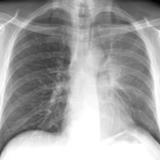

LUL Collapse Case 4 PA

Date: 02/19/2004

Views: 3497